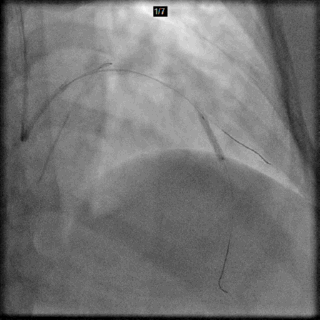

IVUS Co-registration

以IVUS探头位置记录下支架远端落脚点参考位置(无须“冒烟”)

Previous angiogram used as roadmap

以IVUS探头位置记录下支架近端落脚点参考位置(无须“冒烟”)

Stent Deployment

以IVUS探头位置记录下的远端参考位置,作为支架远端落脚点(无须“冒烟”)

3.5x18 以12atm 释放